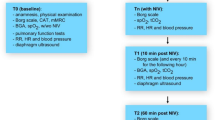

We prospectively recruited healthy volunteers (n = 53), stable outpatients with COPD (n = 40) and patients with hospitalised acute exacerbations of COPD (AECOPD, n = 64). 17 of the AECOPD group returned for repeat evaluation when clinically well at 6–12 weeks. All subjects underwent dynamic 320-slice computed tomography of the larynx and trachea during tidal breathing, enabling quantitation of tracheal area and dimensions (mean ± SD).

Patients requiring hospital admission to Monash Medical Centre, Melbourne, Australia for doctor-diagnosed AECOPD (n = 64) had upper airway CT conducted within 48 h of hospital admission following informed consent. Inclusion criteria for this group were age 40–90 years, a known diagnosis of COPD or a history of >10 pack years smoking with likely COPD (subsequently spirometrically confirmed). All patients had a history of deterioration in COPD symptoms leading to ED admission and severity was classified according to BAP-65 [15]. Exclusion criteria were known tracheal or laryngeal disease, a history of asthma, the inability to be recumbent for 10 min and known obstructive sleep apnoea: these exclusions also applied to the stable COPD group. A subgroup (n = 17/64, 26%) was reassessed 6–8 weeks after AECOPD and upper airway CT repeated.

Patients with AECOPD were studied by repeat imaging when symptomatically recovered (n = 17, clinical characteristics detailed in Additional file 2: Table S2). Mean levels of ECAC in this convalescent group (ratio 54.1 ± 18.9%) were not significantly different to that when they experienced an acute COPD exacerbation (ratio 53.2% ± 17.3%, p = 0.742) Fig. 2).

Percentage tracheal collapse in acute exacerbations of COPD and at convalescence. In the subset of patients who returned for repeat CT scans at convalescence (n = 17), tracheal collapse is similar between acute exacerbations and convalescence. Tracheal collapse was measured as the ratio of expiratory/inspiratory airway area and expressed as a percentage (%)